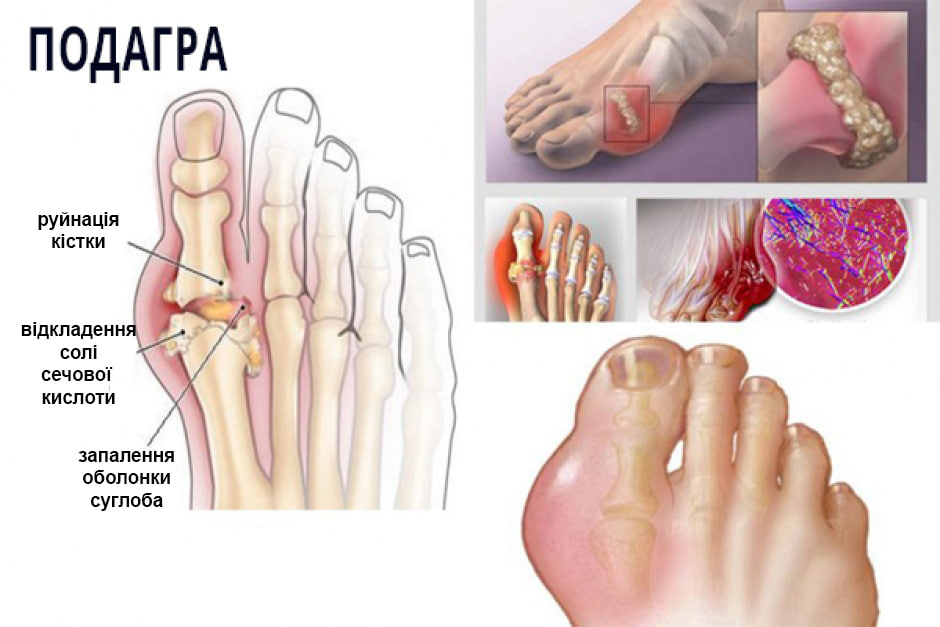

Так розвиваються недуги суглобів: від "невинних" болю й дискомфорту до повної неспроможності рухатися

Суглобові патології - небезпечні та підступні хвороби, що призводять до передчасної втрати здатності рухатися аж до повного знерухомлення й інвалідності.